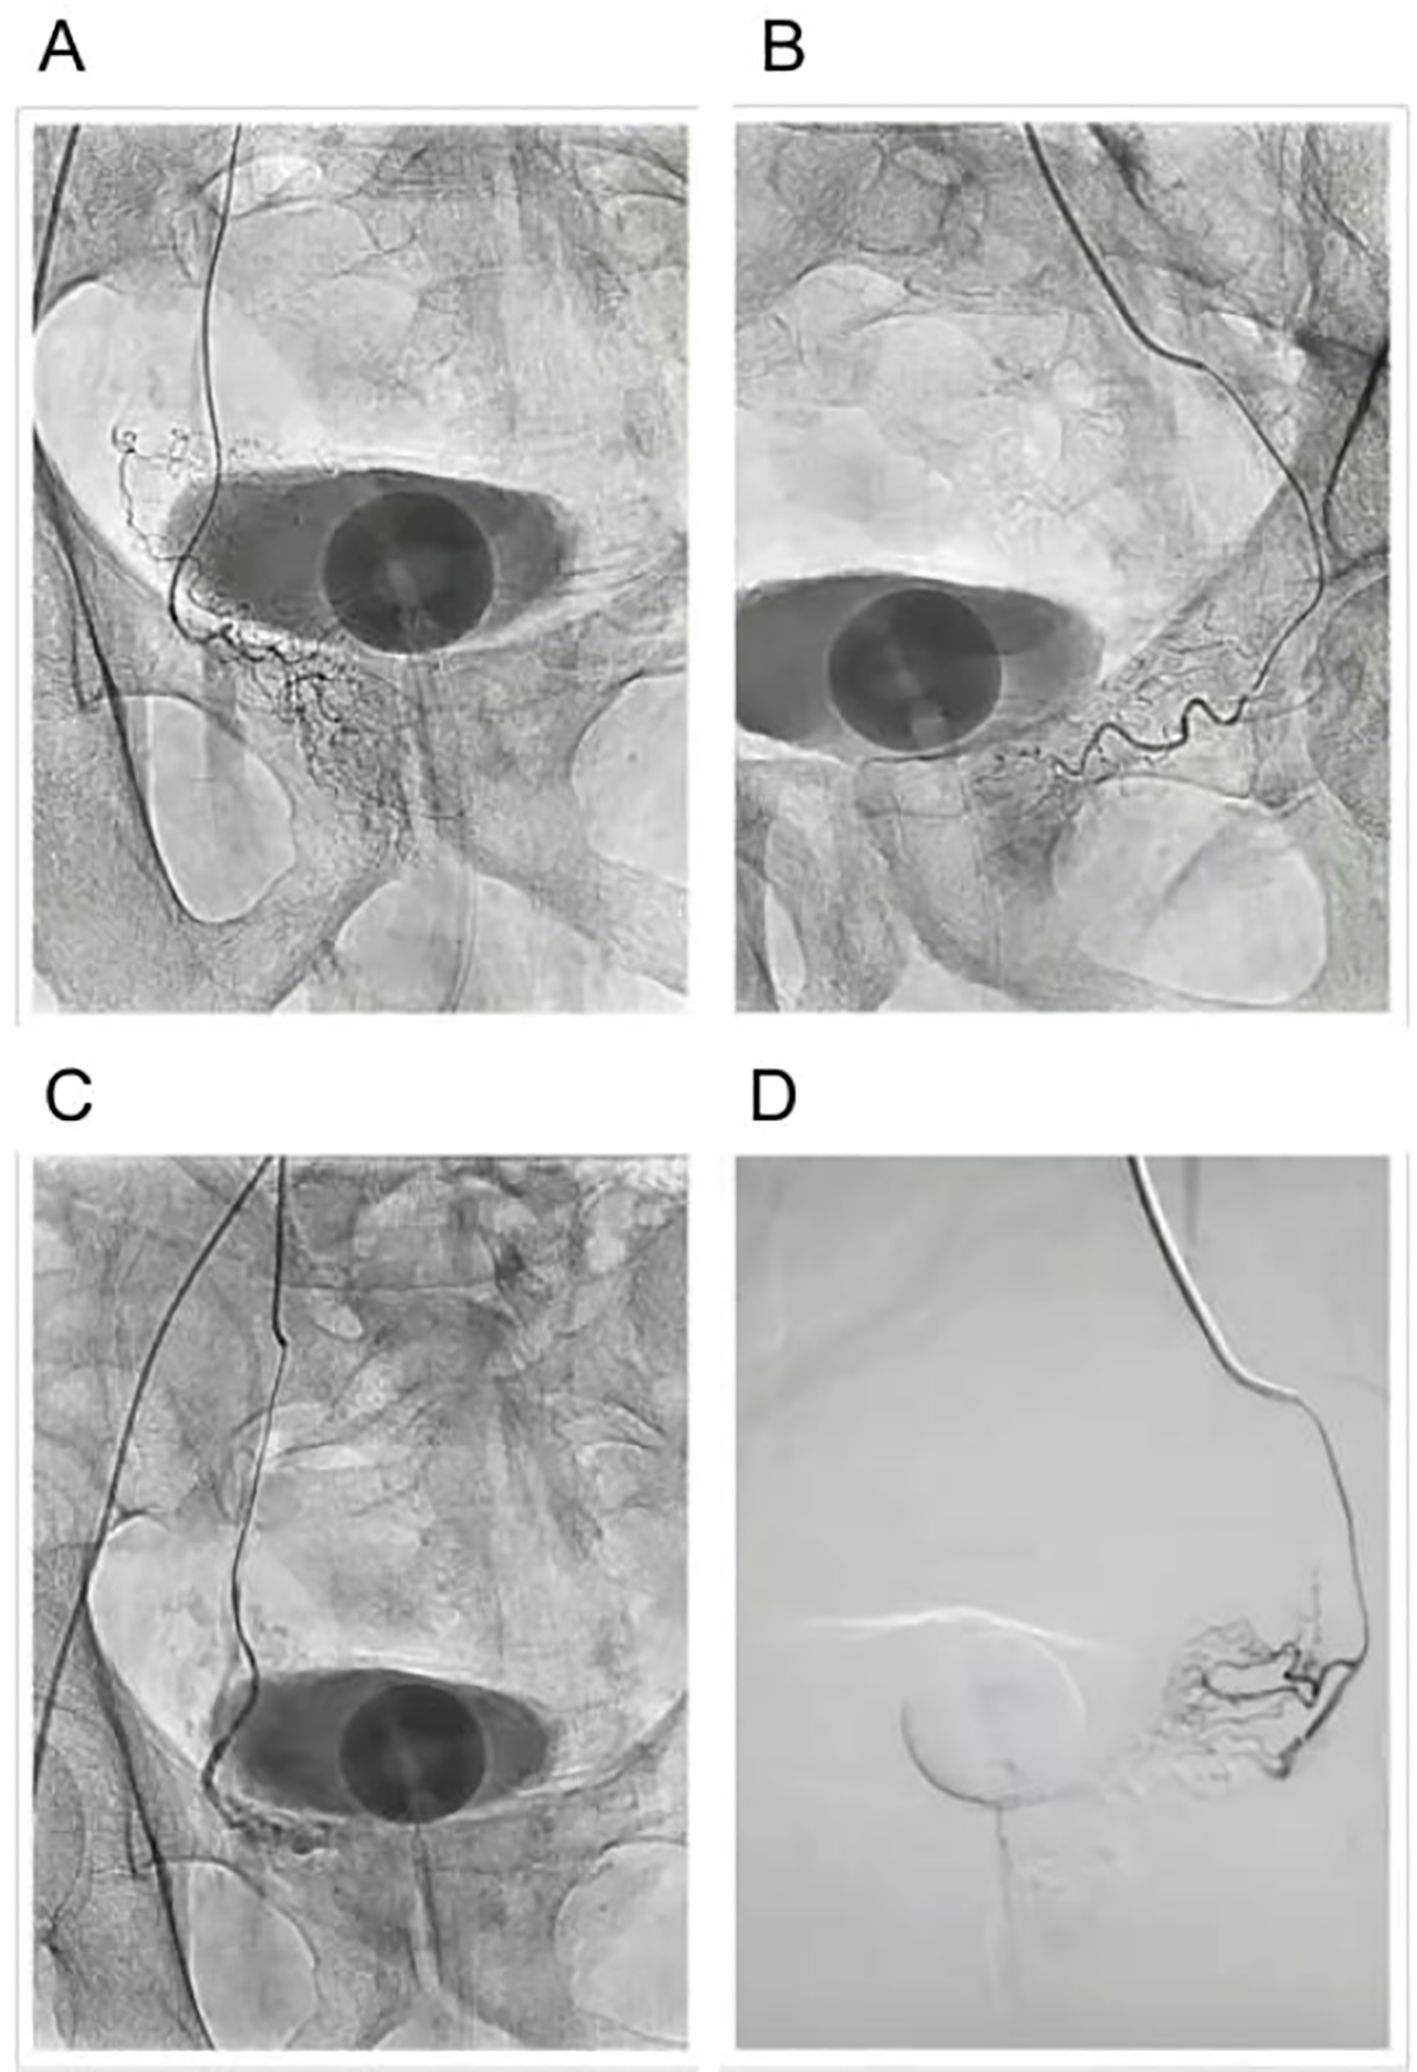

The procedure begins with catheterization of the prostatic arteries, where a small catheter is inserted into the femoral or radial artery and advanced under fluoroscopic guidance to reach the prostatic arterial supply. Once the catheter is correctly positioned, embolization using microparticles follows, where embolic agents such as polyvinyl alcohol (PVA) particles or microspheres are injected into the prostatic arteries. These particles travel through the arterial system and block blood flow to the prostate tissue, effectively reducing the oxygen and nutrient supply needed for prostate growth. Over the course of weeks to months, the ischemic prostate tissue undergoes necrosis, leading to a gradual reduction in prostate volume and subsequent relief of urinary symptoms (Figure 4) (105).

Figure 4

Three endoscopic images labeled A, B, and C show different views of internal anatomy. Image A depicts a clear view of two holding instruments. Image B shows a close-up of a red and white tissue section. Image C highlights a wider view with surrounding tissue. The images demonstrate the surgical process for tracheal resection.

Figure 4. Prostatic arterial embolization (PAE) procedure. (A) Before embolization of the left prostatic artery. (B) Before embolization of the right prostatic artery. (C) After embolization of the left prostatic artery. (D) After embolization of the right prostatic artery.